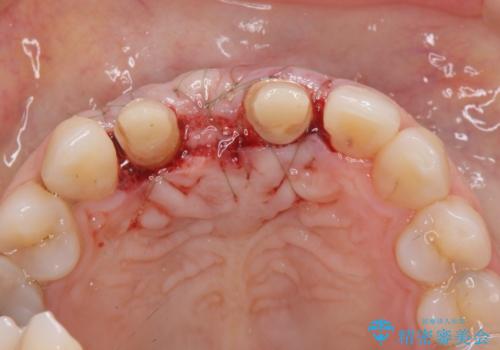

歯周外科をおこなったことで歯ぐきのラインを整え、脱離しないような前歯のブリッジを作製することができました。